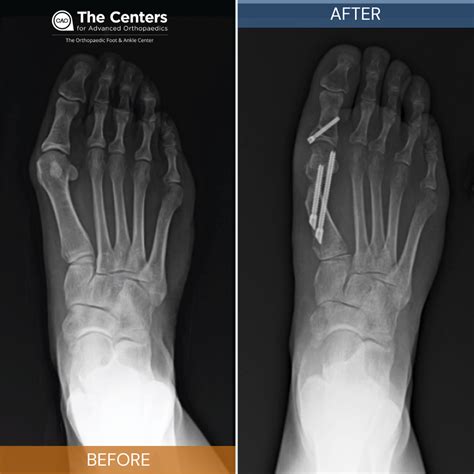

Jeremy Cope Blog